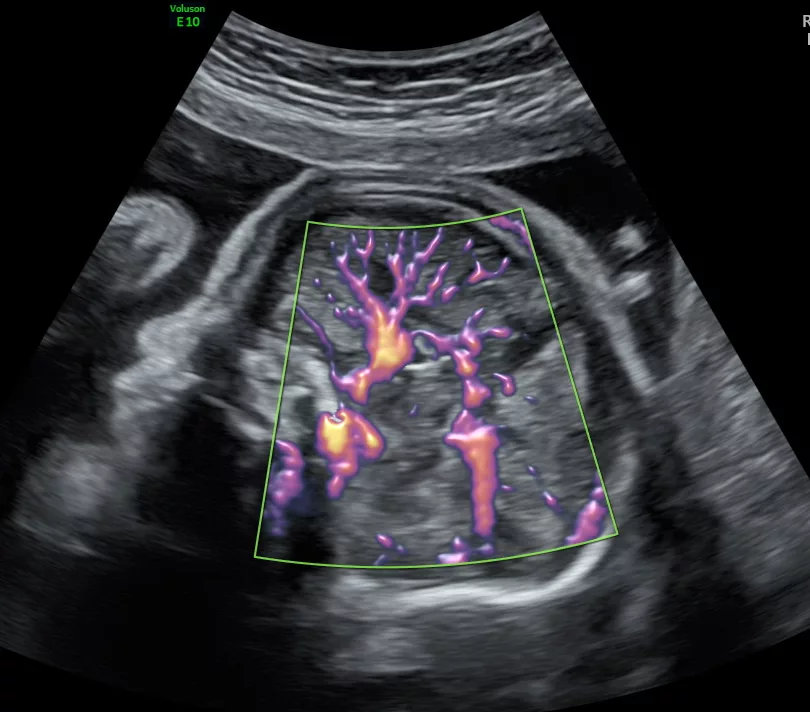

- Prenatal diagnosis of antenatal midgut volvulus: Specific ultrasound features. Bartholmot C,Faure JM, Grosjean F, Couture A, Forgues D, Fuchs F, Prodhomme O. Prenat Diagn. 2019 Jan;39(1):16-25.

- Performance of Prenatal Ultrasound Screening for the Relative Positioning of Mesenteric Vessels. Faure JM, Larroque-Devigne A, Forgues D, Mousty E, Couture A, Kalfa N, Prodhomme O, Fuchs F. J Ultrasound Med. 2024 Sep 11.